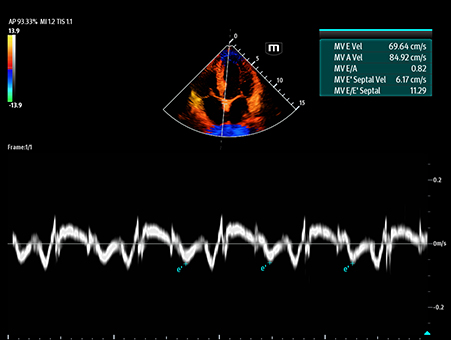

MindrayŌĆśs critical Ultrasound solutions drive improvements in care quality. Integrating advanced hemodynamic Ultrasound features, we can guarantee the highest standard of clinical care. The unique interoperability of Ultrasound and Vital sign data, we can provide comprehensive patient status data, to help inform clinical decisions, enhance clinical efficiency and, ultimately, improve patient outcomes.